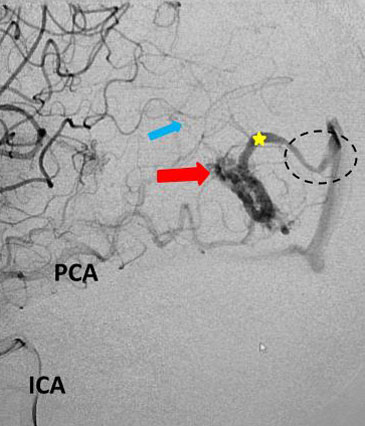

The patient was taken to the angio-suite where an angiogram confirmed a high flow, high pressure AVM fed primarily by the posterior cerebral artery with a small collateral from the middle cerebral artery (Fig 2 and 3). The AVM drained into a tortuous, partially occluded and stenotic single draining vein.

Fig 3. Lateral view, late-arterial phase of a right internal carotid artery (ICA) injection. Filling of the AMV (red arrow) by the fetal posterior cerebral artery (PCA) and small middle cerebral artery feeder (blue arrow). The large tortuous draining vein (yellow star) with venous stenosis and the suggestion of clot (dotted circle) can be seen.